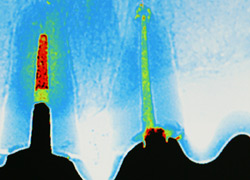

Unsere Praxis ist mit digitalen CCD Röntgensensoren der neuesten Generation ausgestattet. Diese ermöglichen gegenüber der konventionellen zahnärztlichen Röntgentechnik eine Reduktion der Strahlendosis um bis zu 90%. Darüber hinaus sind Auflösung und Kontrastverhalten der Bilder konkurrenzlos. Dies ermöglicht eine extrem schonende und exakte Diagnostik.